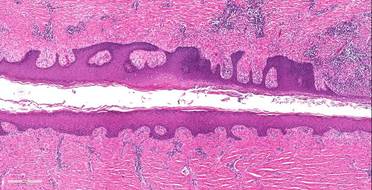

Through the course of the study, researchers found genetic variants pointing to two genes, SOX9 and KLF5, which are thought to play a role in hair follicle and epidermal development. Certain mutations at these loci were more likely to be found in patients with HS than in patients without HS.

The gene SOX9 has two functions in the body: maintaining the structure of the hair follicle and assigning stem cells to become, or differentiate into, the cells that line the hair follicle. SOX9 also triggers the activation of three other genes: MMP1, MMP2, and IL-8, which are linked to the formation of basal cell carcinomas, melanomas, and inflammation.

The other suspected gene, KLF5, promotes the generation of keratinocytes and the secretion of enzymes to eat up dead skin cells. If unchecked, the body produces so much keratin that the epidermis becomes thick and hair follicles can become blocked.

Variations in this gene may explain the development of the characteristic cysts, skin-colored bumps, and tunnels that are seen in patients with HS. Where KLF5 functions to keep epidermal stem cells levels in check, SOX9 is does the same for hair follicle stem cells.

If this careful balance between the expression patterns is disrupted by genetic factors, it may explain why the body forms chronic wounds such as inflammatory tunnels and ulcers, as well as cysts and epithelialized tunnels.